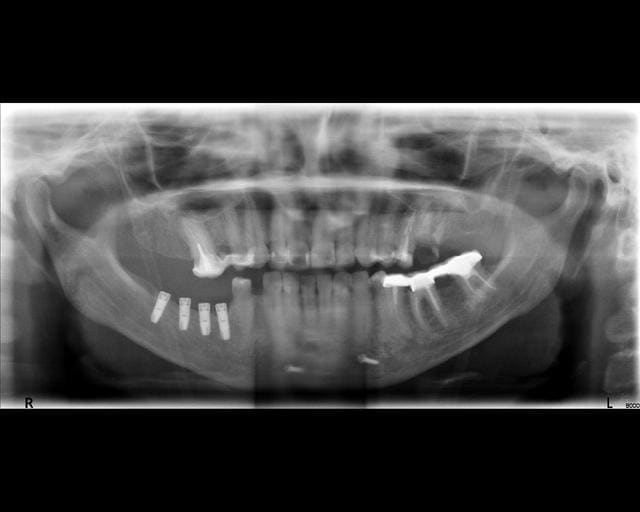

"pas de bras, pas de chocolat"...pas de rétro, pas d'identification

une pano déforme beaucoup et ne nous donne pas assez de détails sur "l'anatomie" des implants, bref çà ne sert à rien dans ce cas de figure qu'est l'identification d'implants...

Je n'ai pas pu avoir mieux.

Je pense à de l'astra

Ça peut être de l'Astra, ou une copie d'Astra... Vu le plan de traitement, et la pose de 4 implants antagonistes à une seule dent, je ne serai pas pressé de m'occuper des implants, il y a tant à faire avant !

non, c'est pas une connexion type Astra

dommage que ta radio ne soit pas plus nette, çà m'aurais permis d'être plus performant...

moi je pencherais plus sur un Alphabio ou même encore plus probable un AB dental

si oui, alors la piste AB est plus que crédible...tu as du récupérer un cas venant de chez Dentexia qui posaient çà à Lyon, et comme maintenant ils sont en liquidation...les patients sont dans la nature...

remarque: les implants sont ostéointégrés...mais pas au mieux de leur forme, il y a déjà une belle cratérisation...

si tu veux faire la prothèse...blinde toi niveau consentement...archive bien les radios, fais signer une décharge avec copie de la radio qui montre le pb déjà avant la prothèse et signé par le patient...